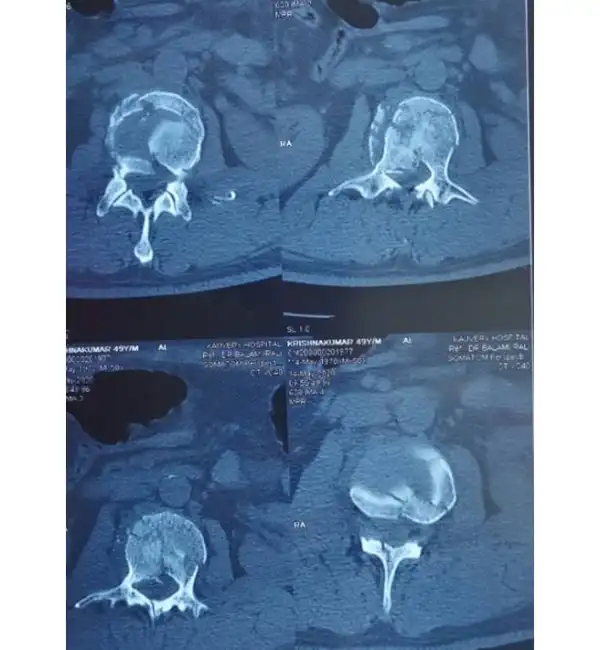

L2 Burst fracture Pre Op CT

C6-7 Fracture dislocation pre op CT